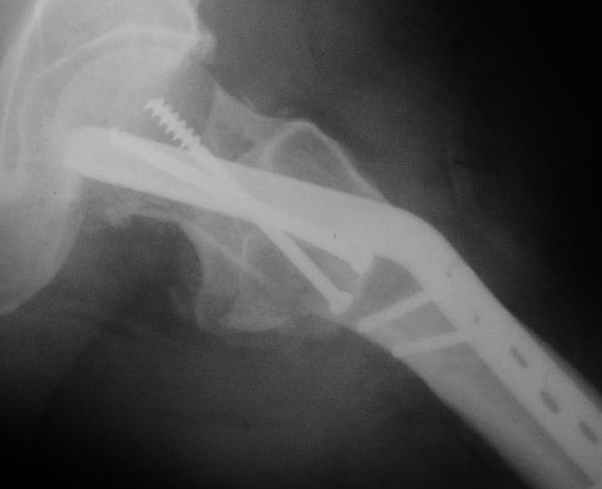

Мужчину 56 лет оперировали у нас в августе 2003 г. - вальгизируюшая остеотомия из-за позднего (через 2 мес. после травмы) поступления с переломом шейки бедра (картинки 1,2). Курильщик, соматической патологии не было. Сейчас поступил с жалобами на проблемы в области тазобедренного сустава, на снимках 3,4 видно вырезывание клинка.

Now he re-admitted with the images 3,4.

What would you do in the situation?